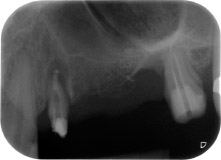

Fig. 1: En una paciente de 58 años, la radiografía previa a la intervención mostraba una lesión periodontal apical en la pieza dental 24, así como una pérdida horizontal de hueso alveolar en el segundo cuadrante.

Mujer de 58 años de edad, que además es una apreciada colega y amiga, y se quejaba de dolor y de un aumento en la movilidad del pilar del puente de la pieza dental 24. También había inflamación periodontal, con bolsas de una profundidad de 7 mm en sentido mesiobucal y más de 12 mm en sentido distal, así como furcación de tercer grado. Asimismo, la radiografía reveló una lesión periodontal extensa alrededor de la región apical de la pieza dental 24 (figura 1) tratada previamente con endodoncia (alio loco).

En la raíz bucal, faltaba todo el hueso vestibular y distal. Básicamente, la fijación se limitó a la raíz palatal, lo que corroboró el mal pronóstico preliminar. La pieza 27 también mostró una fijación horizontal reducida (figura 12) y una rarefacción apical mínima (figura 1), si bien sin síntomas clínicos.

radiografía posoperatoria

Fig. 16: La radiografía posoperatoria muestra ambos implantes en sus posiciones correctas, con material sustituto óseo alrededor de los ápices procedente de la elevación interna del seno. También hay material visible alrededor de las raíces de la pieza 24 procedente del procedimiento de GTR.